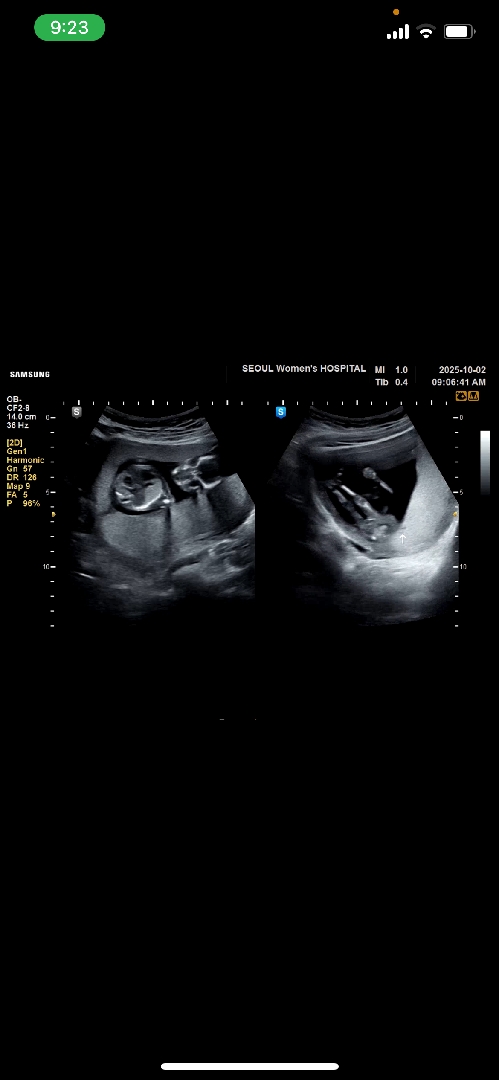

오른쪽에 보이는 두개 쭉 뻗은게 다리 맞나요??? 신랑이 다리라고 아주 확신을 하는뎅ㅎ

쭉 뻗은 다리 맞는거같아용

요게 다리인가요??